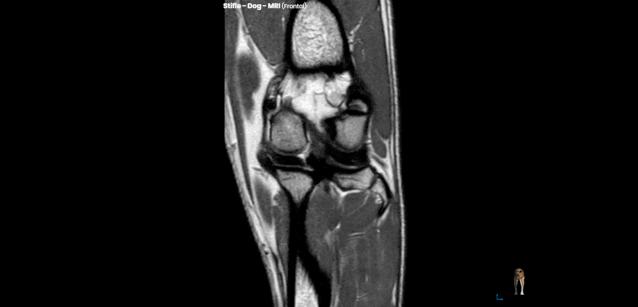

MRI即磁共振成像,又叫做核磁共振。MRI 图像有很高的分辨率,特别对骨和骨之外的软组织具有特殊的鉴别力。MRI 可以很清晰地显示骨周围的肌肉、脂肪、神经、脊髓、韧带等软组织。